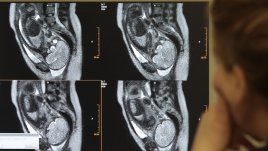

4 строги предписания как бременните да се къпят във вана Полезна ли е ваната през бременността 22.10.2012 | Надежда Маринова